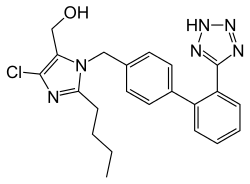

Medical therapy of chronic aortic insufficiency that is stable and asymptomatic involves the use of vasodilators.[2] Trials have shown a short term benefit in the use of ACE inhibitors or angiotensin II receptor antagonists, nifedipine, and hydralazine in improving left ventricular wall stress, ejection fraction, and mass.[3] The goal in using these pharmacologic agents is to decrease the afterload so that the left ventricle is somewhat spared.[30] The regurgitant fraction may not change significantly, since the gradient between the aortic and left ventricular pressures is usually fairly low at the initiation of treatment. Other rather conservative medical treatments for stable and asymptomatic cases include low sodium diet, diuretics, digoxin, calcium blockers and avoiding very strenuous activity.[2]